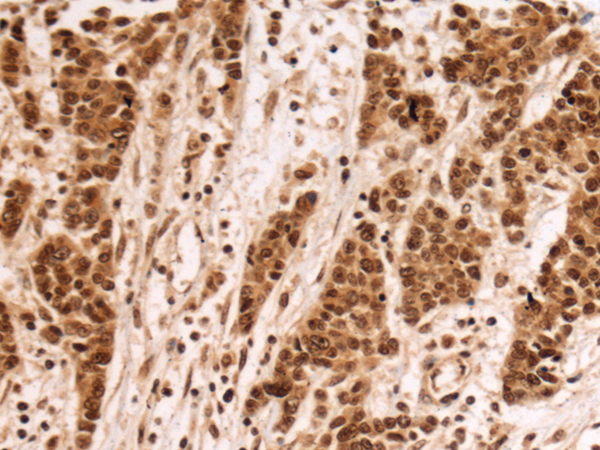

ELISA, IHC

IHC positive control:

Human colorectal cancer and Human esophagus cancer

IHC Recommend dilution:

100-300